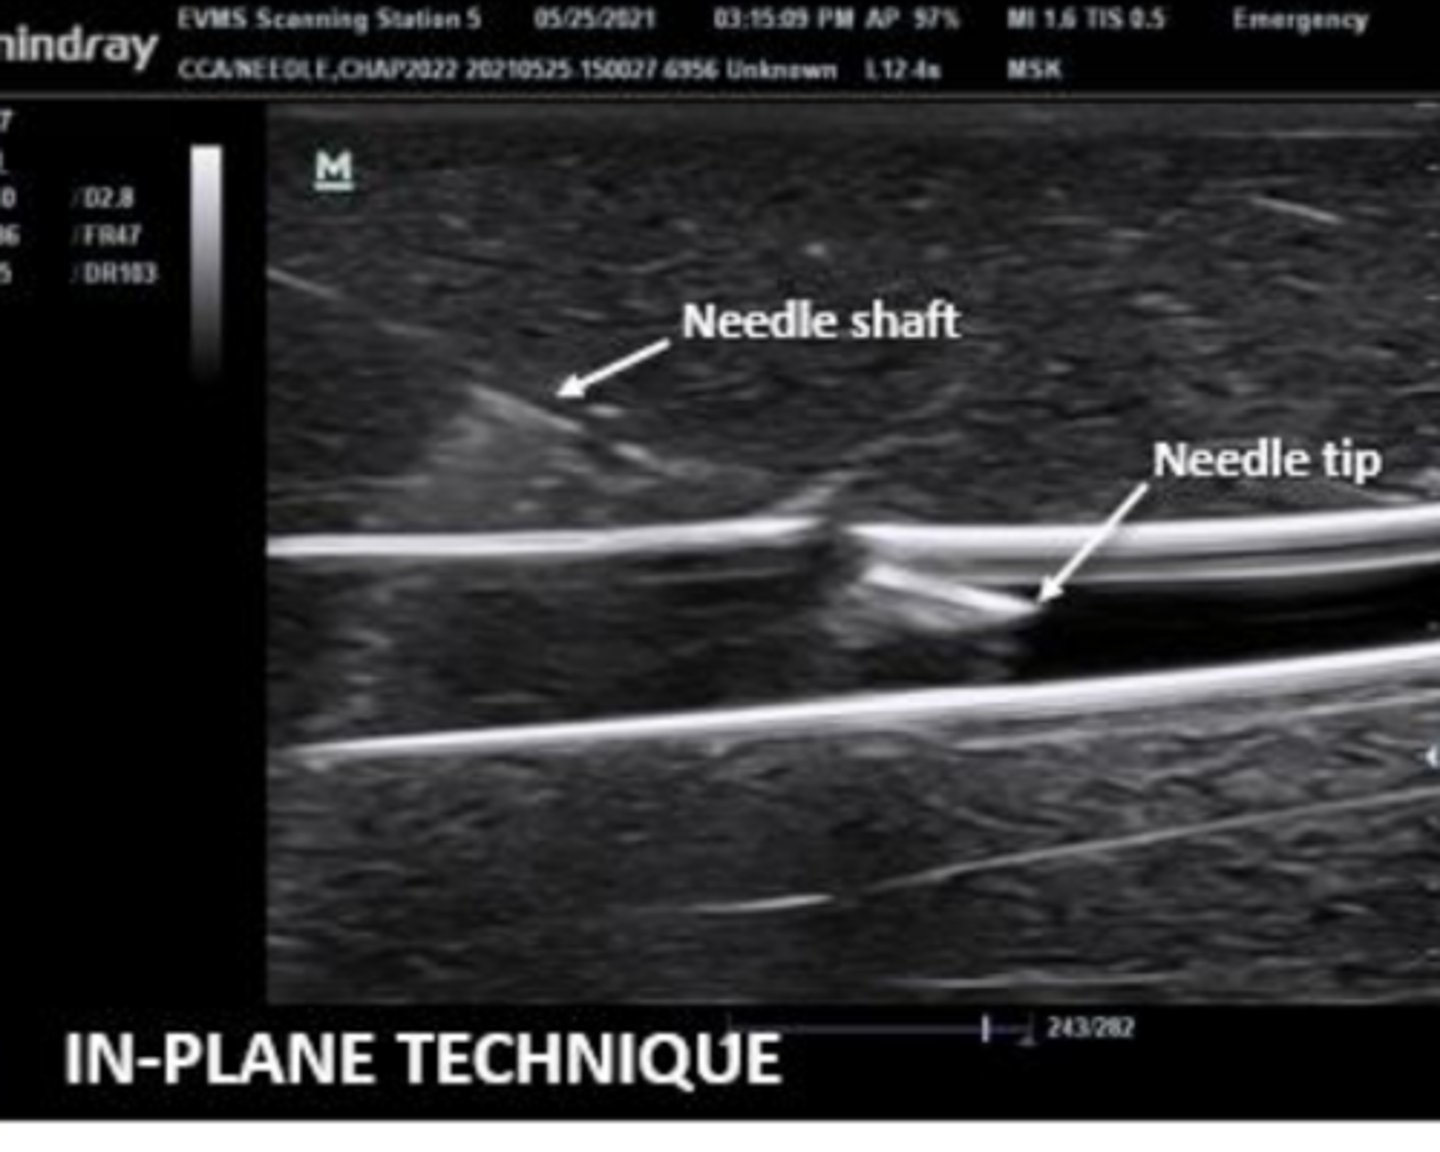

When performing US guided procedures, your ______ hand should be holding the probe

nondominant

Needle should be advanced ______ up

bevel

how do wood, plastic and metal appear on ultrasound

typically hyperechoic

Why should you pull the syringe while advancing the needle?

so that as soon as you see fluid/blood you know to immediately stop advancing

is this an out of plane or in plane view